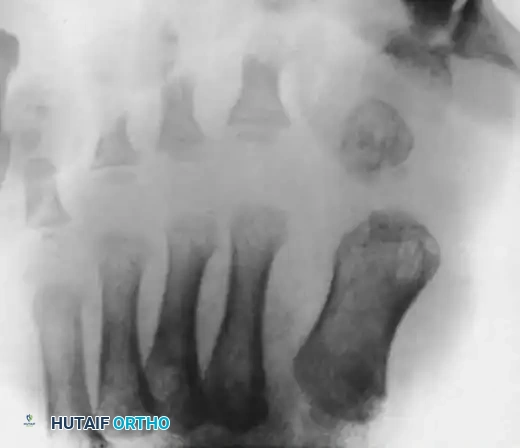

Radiographic Assessment

Standard weight-bearing (or simulated weight-bearing in infants) anteroposterior (AP), lateral, and oblique radiographs of the foot are mandatory.

Key Radiographic Findings:

* Medial subluxation or dislocation of the proximal phalanx on the first metatarsal head.

* A shortened and widened first metatarsal.

* Presence of accessory ossicles, delta phalanges, or rudimentary accessory digits medially.

* Evaluation of the intermetatarsal angle and the alignment of the lesser metatarsals.

Anteroposterior radiograph of a right foot with congenital hallux varus. Note the exceptionally short first metatarsal and the presence of an accessory distal phalanx acting as a medial tether.